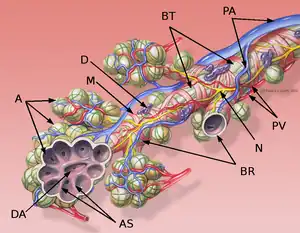

Bases anatomiques

Coloration à l'hématoxyline et à l'éosine (HE).

L'interstitium (tissu de soutien) du poumon est constitué de septums interalvéolaires, situés entre les parois des alvéoles pulmonaires. Ces dernières, siège de l'échange gazeux entre sang et air, forment le tissu proprement fonctionnel du poumon (parenchyme). L'interstitium et le parenchyme coopèrent étroitement au fonctionnement du poumon, et constituent une unité fonctionnelle. L'interstitium constitue l'armature de base du poumon et soutient l'architecture des alvéoles, c'est-à-dire de la barrière sang-air pendant le cycle de la respiration. Cet interstitium est constitué de cellules, avant tout spécialisées dans le soutien (fibroblastes), de protéines structurales qu'elles produisent, et en substances telles que le collagène, les fibres élastiques, les protéoglycanes ainsi que d'autres glycoprotéines.

La majeure partie de l’interstitium est formé par des fibres de collagène, qui forment jusqu'à 20 % de la masse sèche des poumons, en majorité du collagène de type I auquel on doit sans doute le rôle principal pour la conservation de la forme et l’élasticité des alvéoles. On ne trouve le type IV que dans les membranes basales des alvéoles et des vaisseaux sanguins. Les collagènes de types III et V ne sont présents qu’en faible quantité dans le tissu pulmonaire (5 à 10 %)[10]. Les fibres élastiques forment un réseau à connexions multiples dans l'interstitium du poumon. Elles sont la force motrice de l'expiration.

Les protéoglycanes sont responsables de la géométrie du tissu pulmonaire. Leur fonction exacte dans le fonctionnement du poumon n'est pas connue en détail. On trouve dans le poumon de l'acide hyaluronique, du sulfate de chondroïtine A et C, du sulfate de dermatane, de l'héparine et du sulfate d'héparine. En outre, parmi les glycoprotéines, on trouve de la fibronectine et de la laminine, qui apparaissent principalement dans les lames basales.